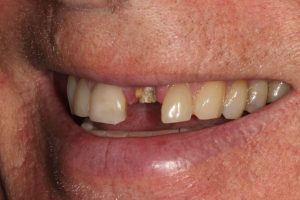

This patient had broken their upper front tooth and the exisitng dental crown had fallen off. The underlying root was unfortunatley irreparable.

The dental root was subsequently removed and an implant placed at the same time. The implant had a temporary crown placedon the same day.

The ‘After’ photos shows the final crown that was made after 3 months. The implant crown was made to match the form and colour of the exisiting teeth to give an overall natural aesthetic finish.